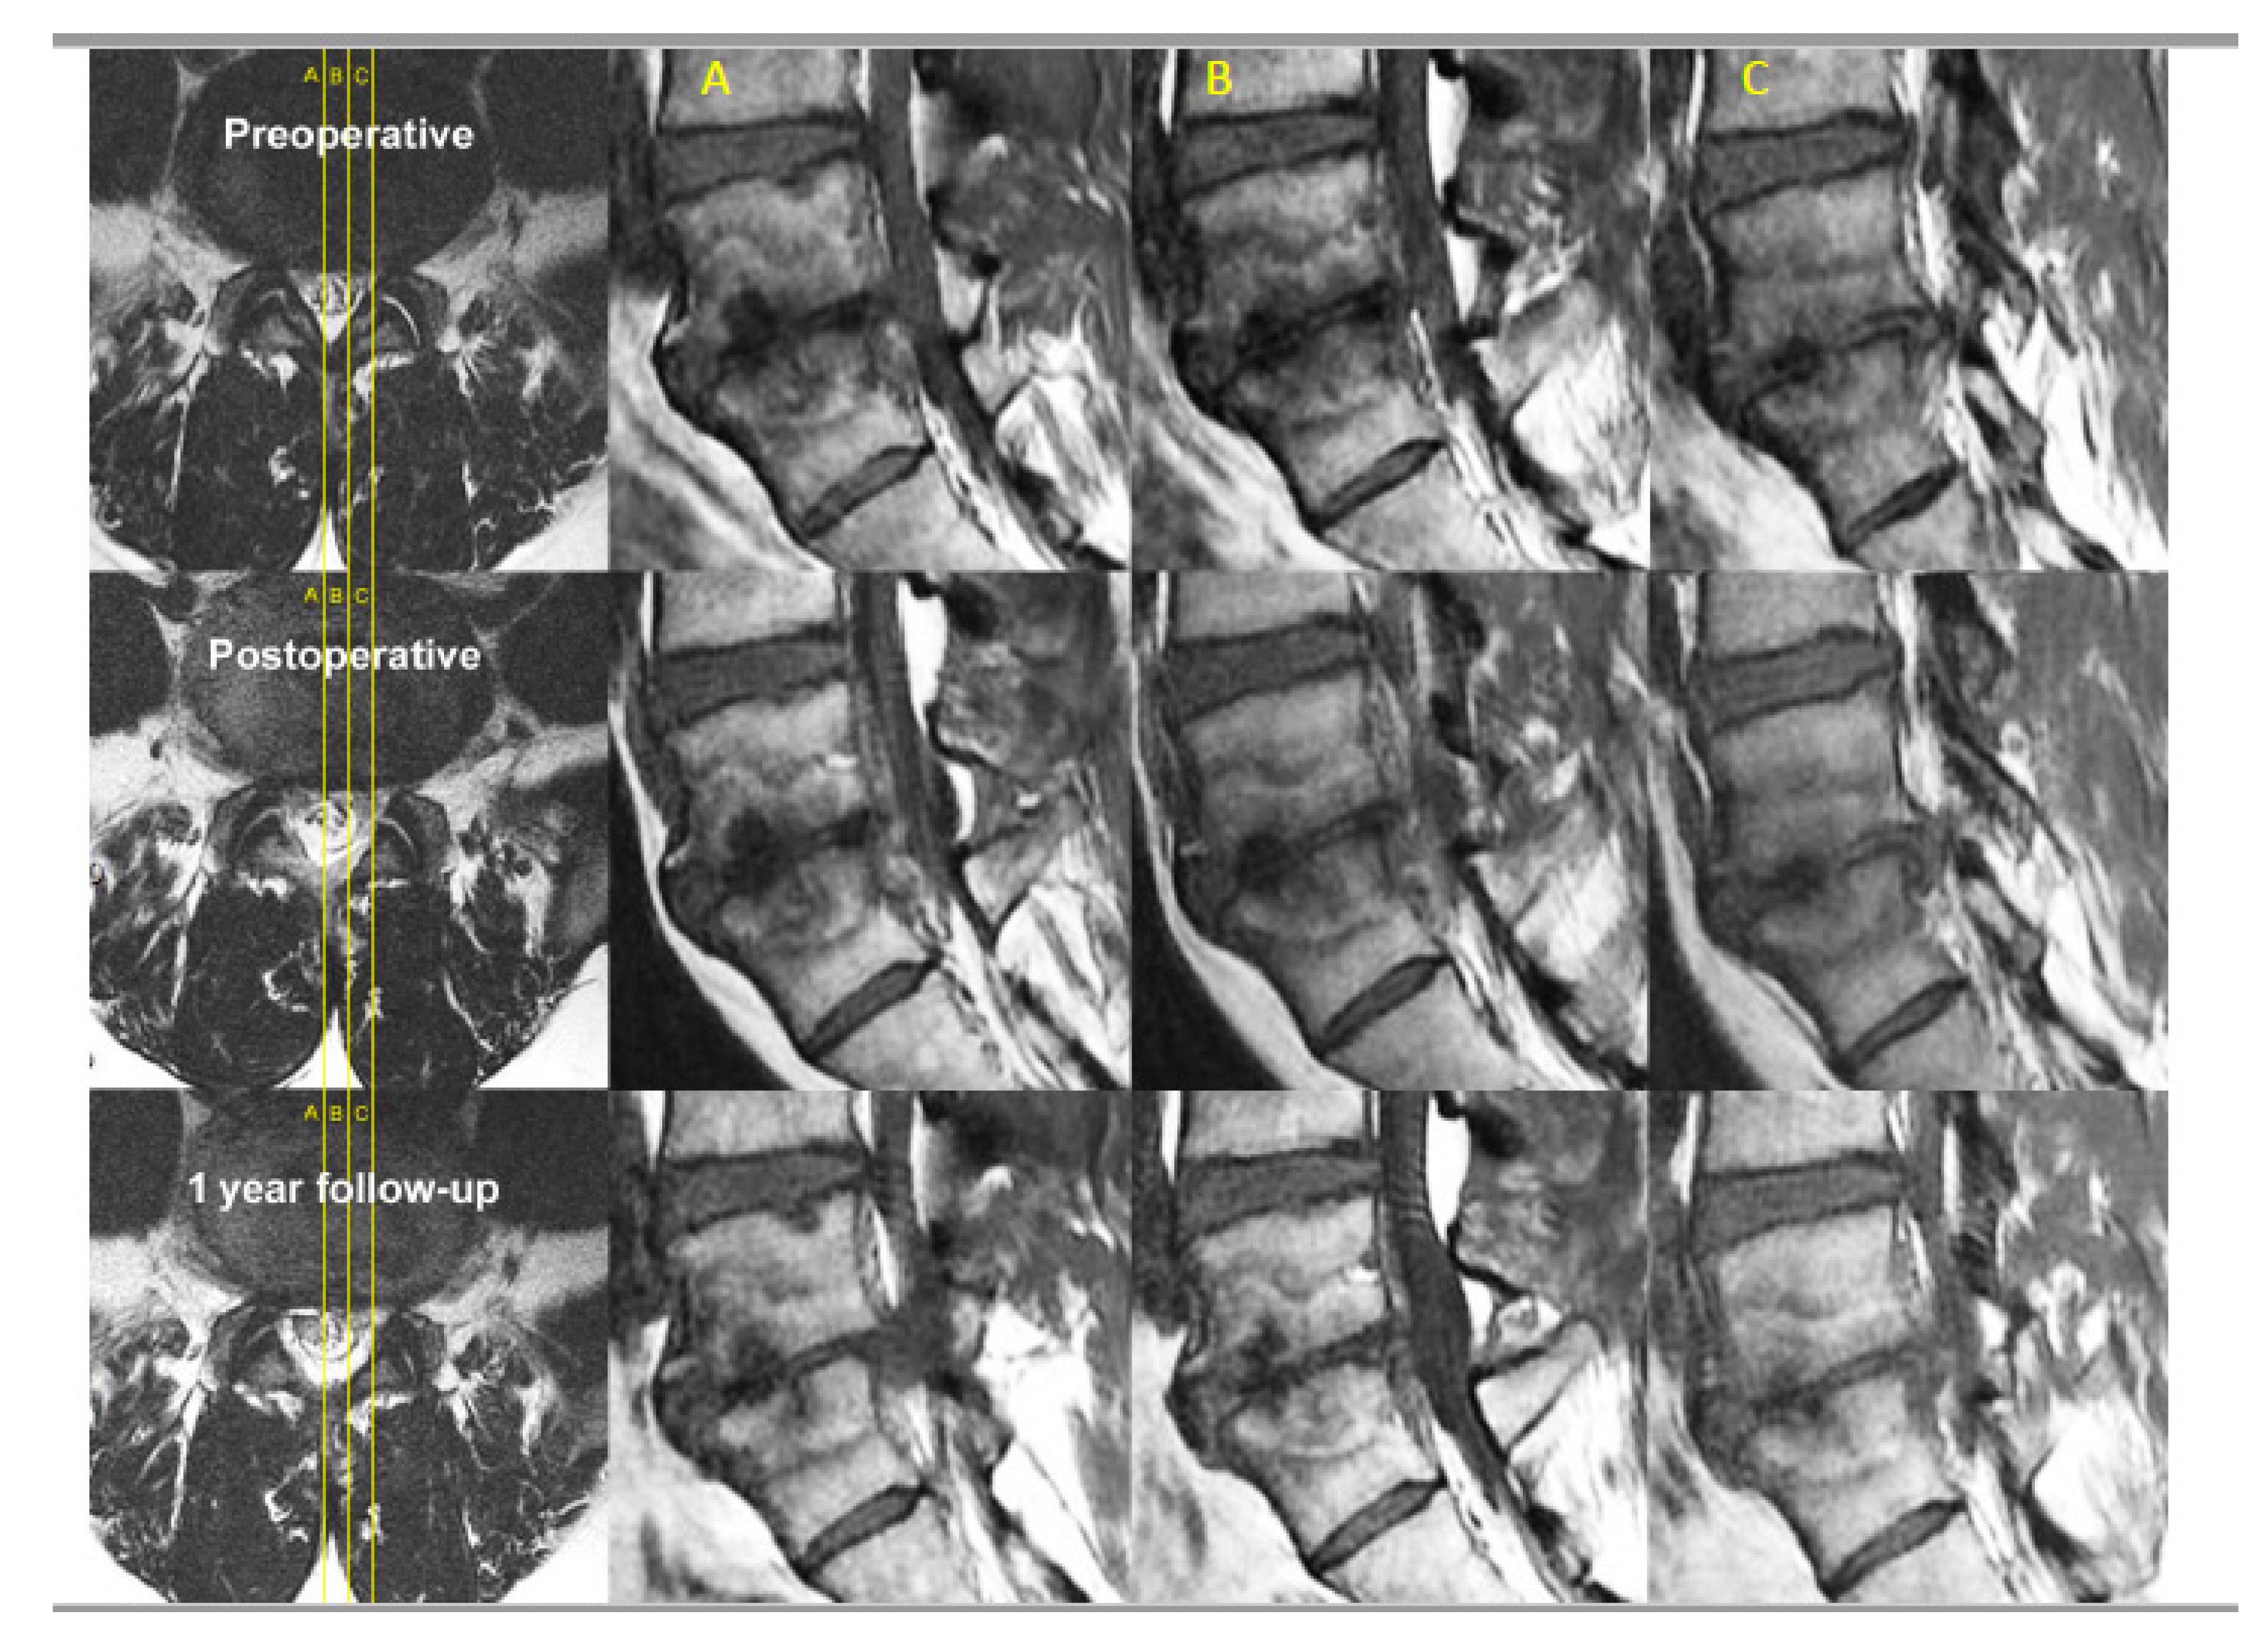

- Kim, H.S.; Adsul, N.; Yudoyono, F.; Paudel, B.; Kim, K.J.; Choi, S.H.; Kim, J.H.; Chung, S.K.; Choi, J.-H.; Jang, J.-S.; et al. Transforaminal Epiduroscopic Basivertebral Nerve Laser Ablation for Chronic Low Back Pain Associated with Modic Changes: A Preliminary Open-Label Study. Pain Res. Manag 2018, 2018, 6857983. [Google Scholar] [CrossRef] [PubMed]

- Choi, S.H.; Adsul, N.; Kim, H.S.; Jang, J.-S.; Jang, I.-T.; Oh, S.-H. Magnetic Resonance Imaging Undetectable Epiduroscopic Hotspot in Chronic Diskogenic Back Pain—Does Sinuvertebral Neuropathy Actually Exist? World Neurosurg. 2018, 110, 354–358. [Google Scholar] [CrossRef]